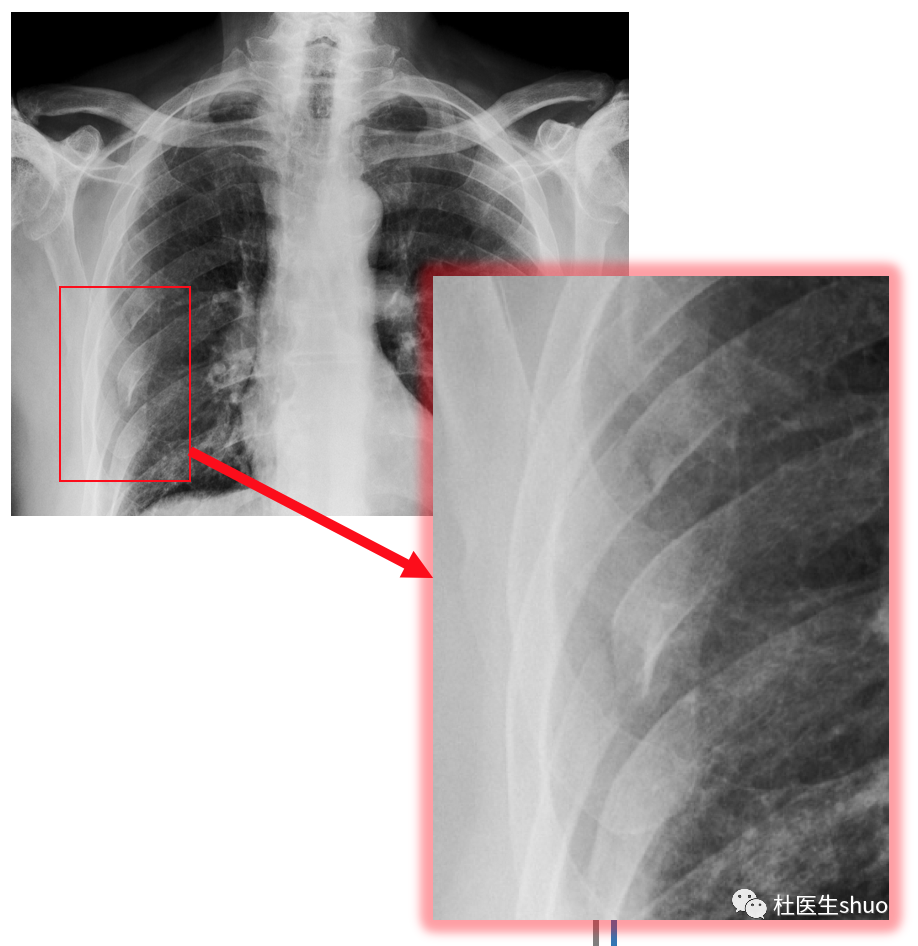

肋骨骨折是常见的损伤,指肋廓骨断裂或出现裂纹。最常见病因是因跌倒、交通事故、撞击或暴力击打。

局部疼痛是肋骨骨折最明显的症状,并且随咳嗽、深呼吸或身体转动等运动而加重,有时患者可自己听到骨摩擦音,或感觉到骨摩擦感。